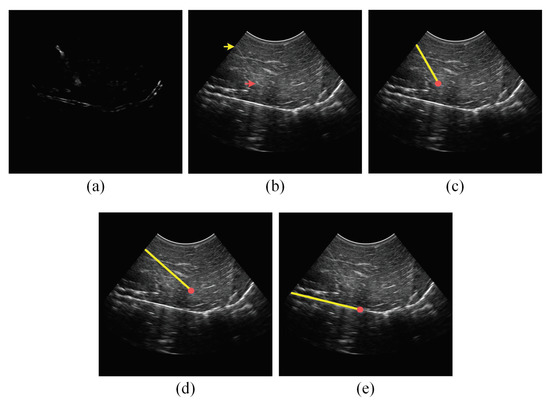

2.2. Analyzing the Power Doppler Ultrasound Image to Obtain an Initial Estimation of the Needle Axis and Identify the Candidate Regions of the Needle

2.3. Analyzing the B-Mode Ultrasound Image to Obtain Accurate Localization of the Needle Axis

2.4. Analyzing the Power Doppler and B-Mode Ultrasound Images to Obtain Accurate Localization of the Needle Tip